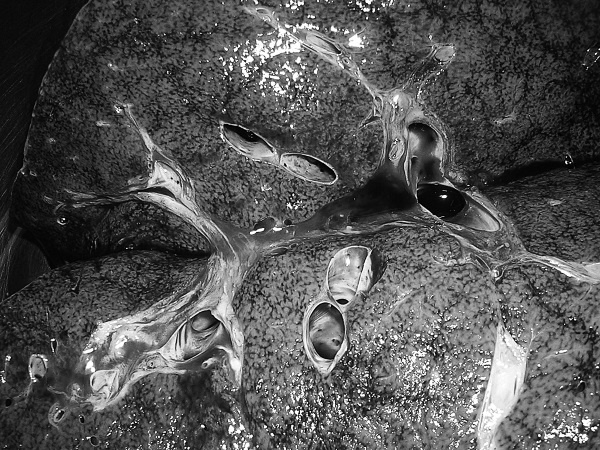

В посмертном эпикризе указан Основной диагноз: последствия ОНМК от 2008 года. ИБС. СН 2. ПИКС. Фоновое: СД 2-го типа, сопутствующее: хронический пиелонефрит. Осложнения: внебольничная пневмония. На секции: ![]() Рис. 31. Последствия перенесенного ОНМК ![]() Рис. 32. Атеросклероз церебральных артерий ![]() Рис. 33. Постинфарктный кардиосклероз ![]() Рис. 34. Гипертрофия миокарда левого желудочка ![]() Рис. 35. Признаки ХСН: мускатный фиброз печени ![]() Рис. 36. Пневмония ![]() Рис. 37. Признаки хронического пиелонефрита Анализируя данный клинический пример, необходимо отметить следующее. 1. Социальный статус. Социальный статус, за исключением указания на участие в ВОВ, не обозначен. 2. Наблюдение на дому. Полное несоблюдение регламента наблюдения ДИП. Клинический диагноз. Записи в амбулаторной карте нет. При этом диагноз должен быть следующим. Основной: последствия ОНМК от 2008 года. ИБС. Постинфарктный кардиосклероз. Фоновое: гипертоническая болезнь 3-й ст., 3 ст. риск 4. СД 2-го типа. Осложнения: длительная иммобилизация. Внебольничная пневмония. НК 2. Хронический пиелонефрит. Анемия. 3. Обоснованность назначения лекарственных препаратов. Терапия СД проводилась вне соответствия с клиническими рекомендациями, контроль за уровнем гликемии не осуществлялся, лечение анемии отсутствовало, вместе с тем при отсутствии подтвержденных данных за пиелонефрит были назначены антибиотики. Таким образом, наряду с указанными замечаниями врач не оценил тяжесть состояния, что не позволило решить вопрос о показанной госпитализации. Приложение № 6 – алгоритм лечения анемии. Приложение № 7 – самоконтроль уровня глюкозы. Пациентка Ф., 84 года. Умерла в январе 2011 года. Иммобилизирована с марта 2010 года в связи с закрытым переломом лонной и седалищной костей. В карте ежемесячные осмотры терапевта в связи с активами СМП. Причина вызовов: гипертонические кризы и болевой синдром. За год до смерти проведены доступные на дому анализы. В плановом порядке в апреле 2010 году проходила стационарное лечение в терапевтическом отделении. Диагноз при выписке: дисциркуляторная энцефалопатия 2-й ст. ГБ. ИБС. СН 3. ПИКС от 2001 года. Железодефицитная анемия. Закрытый перелом лонной и седалищной костей справа. Амбулаторно после стационара принимала энап Н и винпоцетин. В посмертном эпикризе указан Основной диагноз: 1) дисциркуляторная энцефалопатия 2-й ст. и ИБС. СН 3. ПИКС от 2001 г. НК 2А. Фоновое: ГБ. Сопутствующее: хроническая железодефицитная анемия. Закрытый перелом лонной и седалищной костей от 11.03.2010. ![]() Рис. 38. Повторный инфаркт головного мозга ![]() Рис. 39. Постинфарктный кардиосклероз ![]() Рис. 40. Атеросклероз коронарных артерий ![]() Рис. 41. Проявления НК: мускатный фиброз печени ![]() Рис. 42. Острые эрозии желудка ![]() Рис. 43. Атеросклероз аорты Замечания к ведению больного следующие: 1. Социальный статус. Информации нет. 2. Наблюдение на дому. Посещение терапевта осуществлялось только в связи с активами СМП. 3. Клинический диагноз. Нет правильной формулировки диагноза. При этом правильный диагноз был бы следующим. Основной диагноз: 1) Повторный инфаркт головного мозга. 2) ИБС. Постинфарктный кардиосклероз от 2001 года. Фоновое: гипертоническая болезнь 3 ст., 3 ст. Осложнения: закрытый перелом лонной и седалищной костей от 11.03.2010. Длительная иммобилизация. НК 2. Острые эрозии. Хроническая железодефицитная анемия. Сопутствующие: атеросклероз аорты. 4. Обоснованность назначения лекарственных препаратов: лекарственная монотерапия ГБ эналаприлом неэффективна, что повлекло за собой неоднократные гипертонические кризы и вызовы СМП, нет лечения проявлений ПИКС и анемии. Таким образом, не было оценки тяжести состояния, наличия тяжелой степени АГ у больной с перенесенным ОНМК и инфаркта миокарда, кризовым течением и признаками СН, что требовало госпитализации пациента. Приложение № 8 – ведение больного, перенесшего инфаркт миокарда. Пациентка Б., 95 лет. Иммобилизирована. Карта малоинформативна. Осмотры терапевта 1–2 раза в год, лист впервые выявленных диагнозов не ведется. Анализы отсутствуют. Известно, что наблюдалась с диагнозом ИБС, ЦВБ. Хронический бронхит. ОНМК с левосторонним гемипарезом и перелом шейки бедра без указания давности. В карте имеются указания на пролежни. За последние 2 года до смерти терапевтом были назначены: пирацетам, предуктал, мексидол, проведен курс ЛФК на дому. Посмертный эпикриз отсутствует. На секции: ![]() Рис. 44. Последствия перенесенного инфаркта головного мозга ![]() Рис. 45. Постинфарктный кардиосклероз |